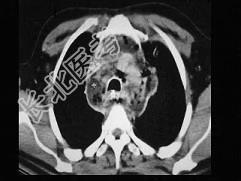

- 单项选择题男,64岁, 患糖尿病,最近三天出现发热, 伴颈静脉显露,结合CT图像, 选择最可能的诊断 ( )

A、坏死性纵隔炎

B、纵隔淋巴瘤

C、侵袭性胸腺瘤

D、恶性畸胎瘤

E、纵隔脓肿